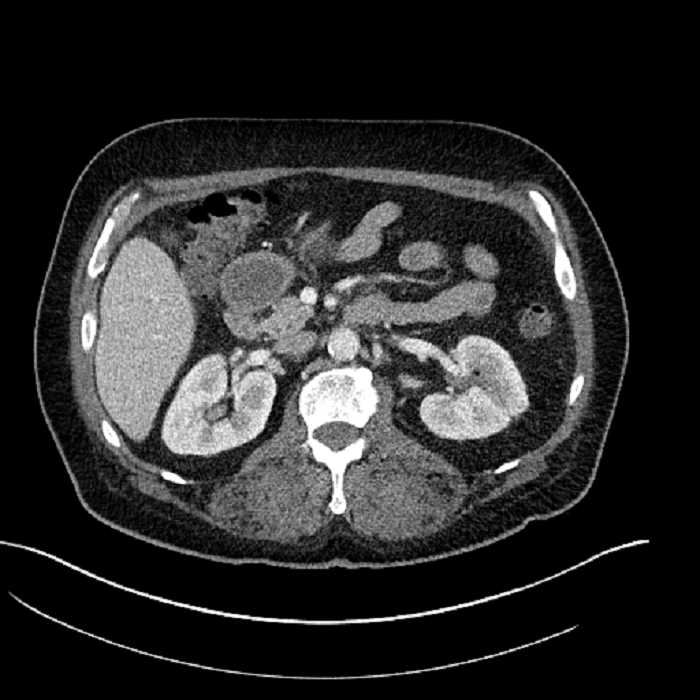

• Large fluid density structure in hepatic segments 7 and 8 measuring 10 x 7 x 7 cm with internal septation and circumferential ill-defined low density compatible with edema

• Peripherally enhancing subcapsular collections along the anterior margin of the left hepatic lobe measuring 3 x 1 cm and 2 x 1 cm

• Clearly marginated fluid density structure in segment 7 and several other scattered tiny hypodensities, which likely represent cysts

Acute sigmoid diverticulitis complicated by a small contained perforation and a large abscess in the right hepatic lobe. Additional small subcapsular abscesses along the anterior margin of the left hepatic lobe.

• The classic CT imaging appearance is a double target sign with internal low density surrounded by an internal enhancing rim (capsule) and a low density external rim (edema)

Hepatic abscess showing the double target sign with low density internally surrounded by a thin inner enhancing rim (red arrow) and ill-defined outer low density rim (yellow arrow). Blue arrow indicates an internal septation. Red arrows: additional smaller subcapsular abscesses. Red arrow: focal contained perforation associated with diverticulitis.